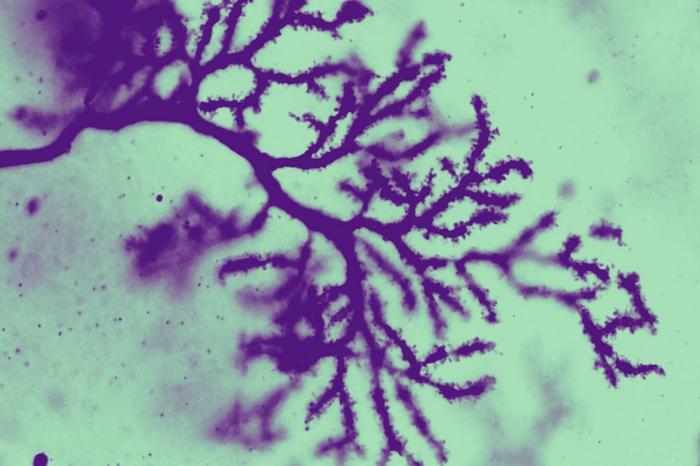

Purkinje cells in the cerebellum, stained and magnified 63 times, revealing fine details of the dendritic spines.

Credit: Laboratory of Developmental Neurobiology at The Rockefeller University

When they analyzed the brains of the ASTN2 mice, they found a few small but apparently potent structural and physiological changes in the cerebellum. One was that large neurons called Purkinje cells had a higher density of dendritic spines, structures that are spotted with the synapses that send neural signals. But they only detected this change in distinct areas of the cerebellum. “For example, we found the biggest difference in the posterior vermis region, where repetitive and inflexible behaviors are controlled,” Hanzel says.